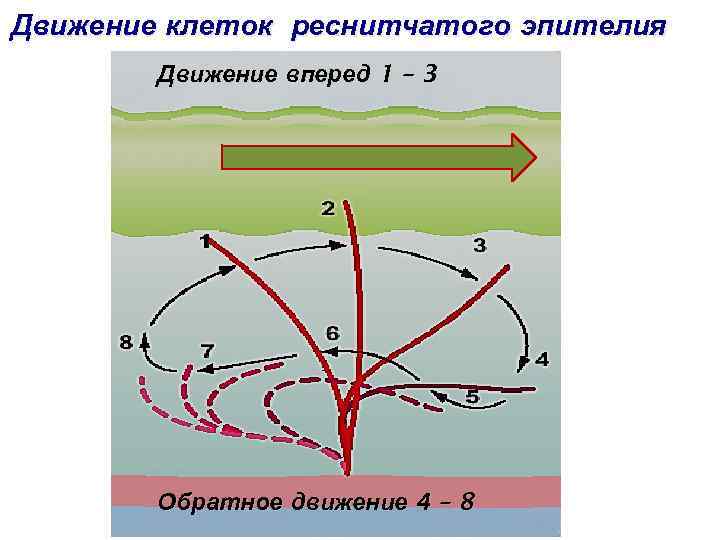

Движение клеток реснитчатого эпителия Движение вперед 1 – 3 Обратное движение 4 – 8

Движение клеток реснитчатого эпителия Движение вперед 1 – 3 Обратное движение 4 – 8